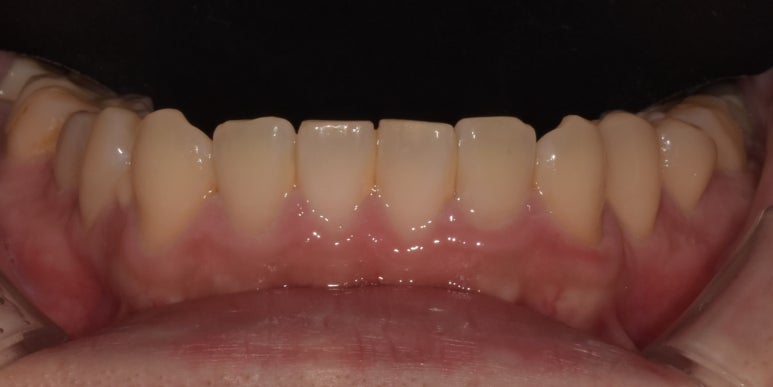

20231107 아랫니 라미네이트 전

20231120 아랫니 라미네이트 후